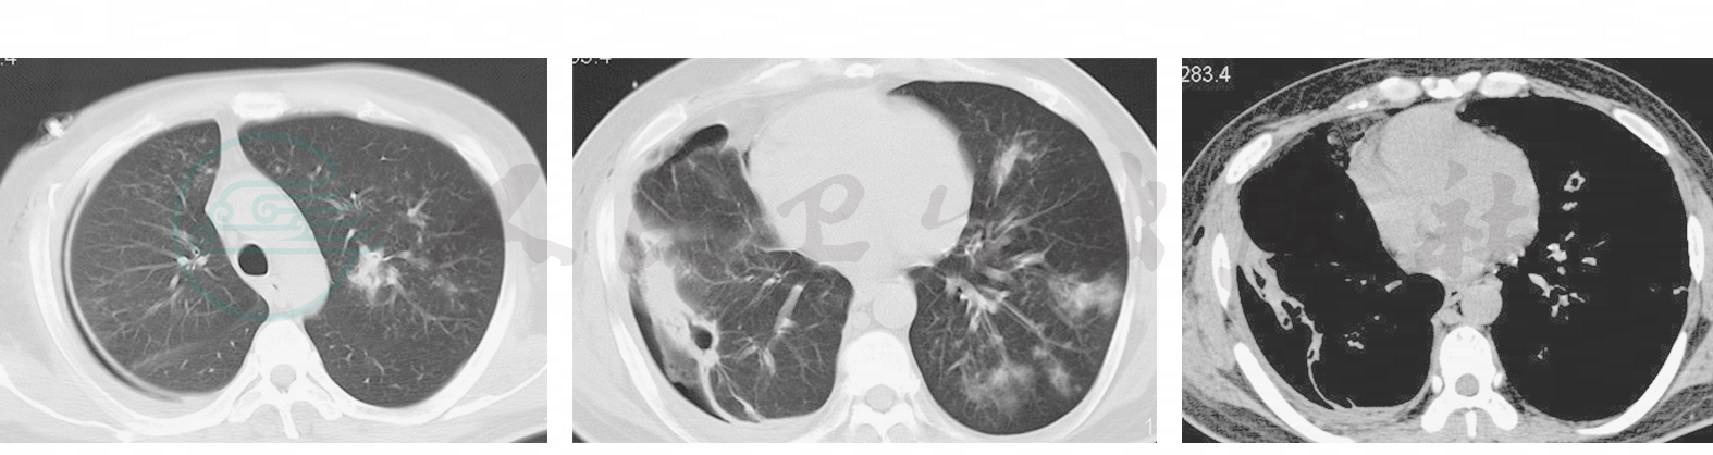

8月15日患者再次发热,体温最高达40.6℃,仍有咳嗽,黄黏痰较前增多,胸腔内每天仍引流出200ml左右脓液,予停用左氧氟沙星、头孢吡肟、甲硝唑,改为氟康唑0.4g,每日1次,抗真菌治疗。胸腔内生理盐水冲洗。此后患者咳嗽逐渐减轻,痰量减少,引流液逐天减少,体温有所下降,血常规好转,血糖稳定。8月25日复查胸部CT示:右侧脓腔明显缩小,但左肺出现新的病灶(图6)。

图6 2009-8-25胸部CT:右侧脓腔明显缩小,但左肺出现新的病灶

继续积极冲洗胸腔及抗真菌治疗,引流液逐渐转清,多次复查胸腔积液培养阴性,监测肝功能无明显异常。9月23日复查胸部CT示:右侧脓腔基本闭合,左肺病灶较前吸收(图7)。9月25日体温37.6℃,拔除右胸腔闭式引流。经过积极历时100余天的综合治疗,患者无明显咳嗽、咳痰,气促缓解,双肺啰音消失,呼吸衰竭纠正,血糖稳定。10月26日复查胸部CT示双肺炎症较前明显吸收(图8),于10月28日出院,出院后继续氟康唑治疗6个月。2010年3月15日患者门诊随访,一般情况好,肺通气功能正常,门诊随访复查胸部CT示双肺见少许条索状阴影(图9)。

图7 2009-9-23胸部CT:右侧脓腔基本闭合,左肺病灶较前吸收

图8 2009-10-26胸部CT:双肺炎症较前明显吸收

图9 2010-03-15胸部CT:双肺见少许条索状阴影